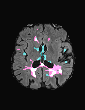

In recent years, data-driven machine learning (ML) methods have revolutionized the computer vision community by providing novel efficient solutions to many unsolved (medical) image analysis problems. However, due to the increasing privacy concerns and data fragmentation on many different sites, existing medical data are not fully utilized, thus limiting the potential of ML. Federated learning (FL) enables multiple parties to collaboratively train a ML model without exchanging local data. However, data heterogeneity (non-IID) among the distributed clients is yet a challenge. To this end, we propose a novel federated method, denoted Federated Disentanglement (FedDis), to disentangle the parameter space into shape and appearance, and only share the shape parameter with the clients. FedDis is based on the assumption that the anatomical structure in brain MRI images is similar across multiple institutions, and sharing the shape knowledge would be beneficial in anomaly detection. In this paper, we leverage healthy brain scans of 623 subjects from multiple sites with real data (OASIS, ADNI) in a privacy-preserving fashion to learn a model of normal anatomy, that allows to segment abnormal structures. We demonstrate a superior performance of FedDis on real pathological databases containing 109 subjects; two publicly available MS Lesions (MSLUB, MSISBI), and an in-house database with MS and Glioblastoma (MSI and GBI). FedDis achieved an average dice performance of 0.38, outperforming the state-of-the-art (SOTA) auto-encoder by 42% and the SOTA federated method by 11%. Further, we illustrate that FedDis learns a shape embedding that is orthogonal to the appearance and consistent under different intensity augmentations.